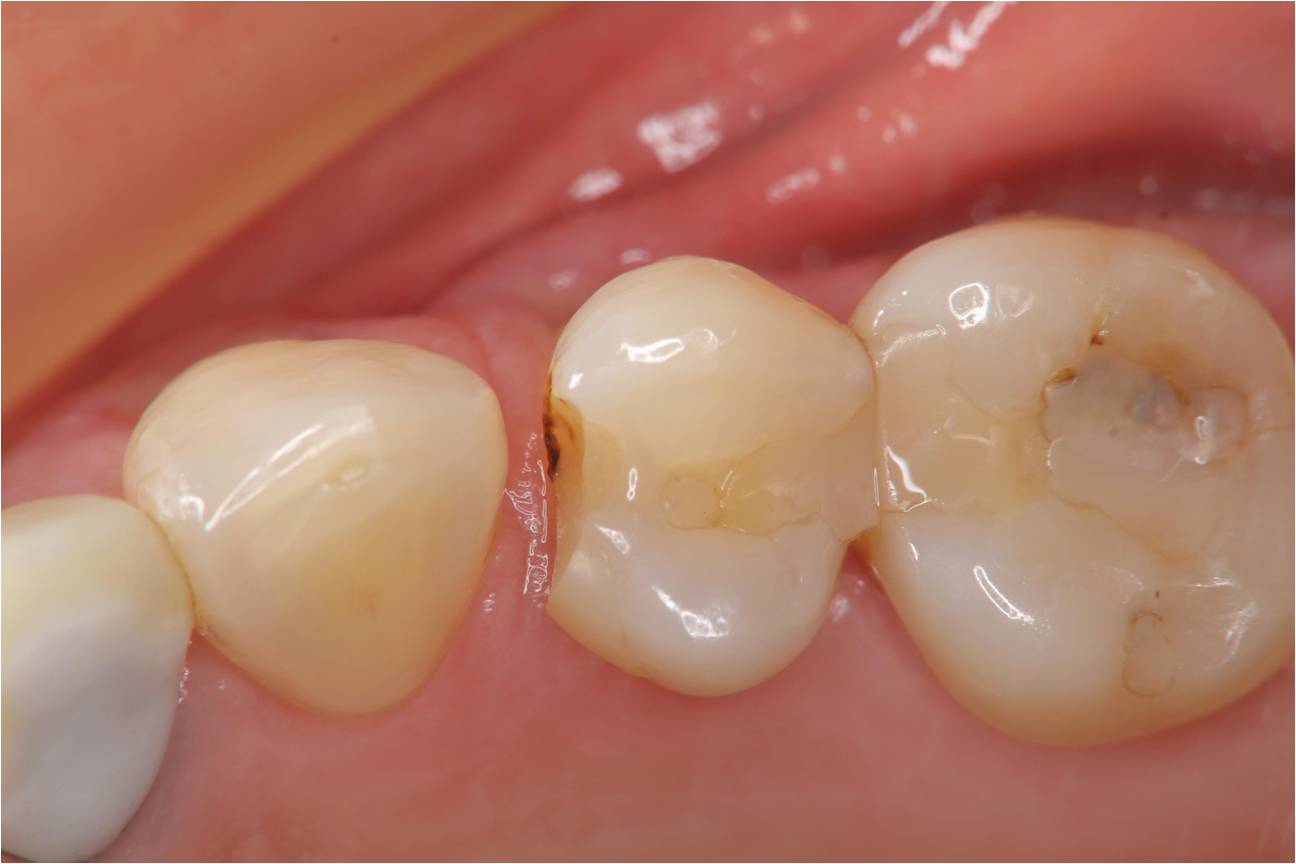

治療前,小臼齒二次蛀牙,牙崩

二次蛀牙,牙髓未受侵犯